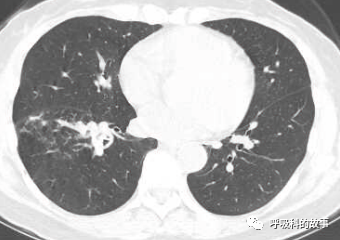

1個月前,黃女士來到了杭州市第一人民醫院呼吸科,找到我看病,我給她複查了肺部CT,如下:

初一看,好像就是普通的肺炎,可是為什麼相隔兩個月在同一部位反覆發生呢?另外,右下葉肺門較左側明顯增大,感覺到管腔似乎也不是那麼清爽,於是我繼續開啟縱隔窗繼續檢視影像情況。

這一看嚇我一跳,患者右下葉支氣管腔內有高密度影,這讓我首先想到的就是支氣管異物堵塞管腔,從而引起阻塞性肺炎。於是我在認真檢視後,嚴肅地對患者說要住院。黃女士可能一來工作繁忙,二來對我的診斷可能表示懷疑,因為她記憶裡沒有誤吸的事件發生,三來以前的CT報告也沒有提示支氣管異物,於是要求繼續口服藥物治療。